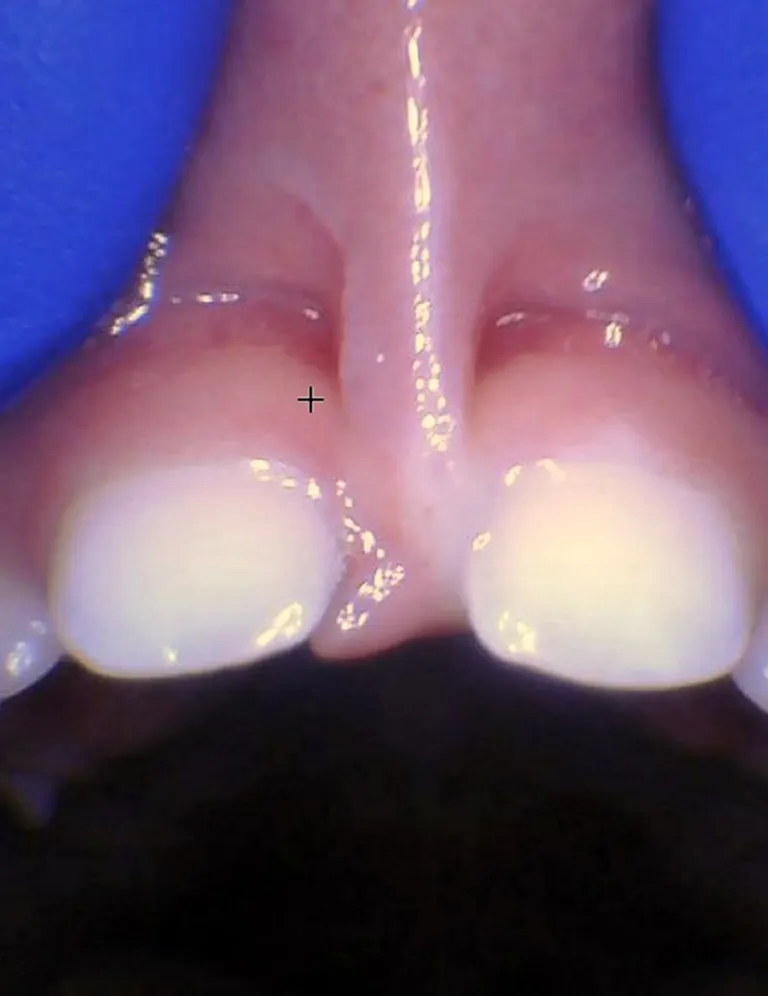

Bébé - Spectre de restrictions d'un FR labial

Enfant - Spectre de restrictions d'un FR labial